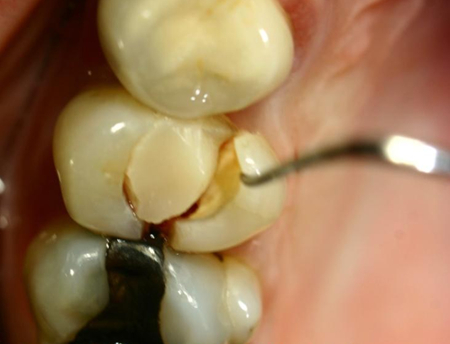

O atrito relacionado ao bruxismo que atinge a dentina pode resultar em dor e hipersensibilidade dentária

Da coleção do Dr. Alessandro Bracci